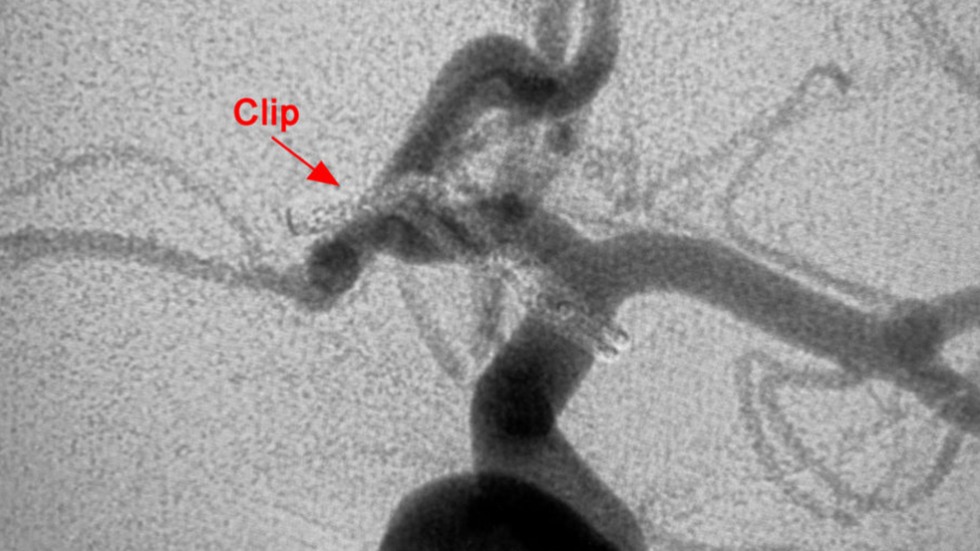

Surgical Clip

2 of 3

After Surgical Clipping

3 of 3